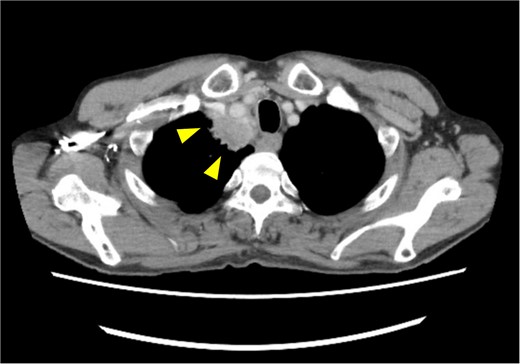

A 72-year-old man diagnosed with NSCLC was referred for possible surgical treatment of a solitary nodule detected in the mesorectum. His medical history included hypertension and endoscopic resection of colonic polyps, with no prior thromboembolism. He had received combined medical treatment for NSCLC (cT4N0M0, stage IIIA) (Fig. 1), including four courses of cisplatin and docetaxel chemotherapy with a 60 Gy/30 fractions radiation dose, followed by 1 year of consolidation therapy with durvalumab (640 mg/body). The patient tolerated the treatment well, achieving a complete response 13 months before presentation (Fig. 2). However, the mesorectal nodule was incidentally discovered during surveillance CT after NSCLC treatment completion. It was round, 15 mm in diameter, showed contrast enhancement, and was near the mesorectal vessels (Fig. 3a and b). An FDG PET/CT scan revealed a solitary mesorectal nodule with an SUVmax of 10.3 (Fig. 4). Consequently, the radiologist suggested differential diagnoses of malignant lymphoma and metastatic lymph nodes from the urinary or lower gastrointestinal tract, as NSCLC typically does not metastasize to mesorectal lymph nodes. No other abnormal FDG uptake was observed. Laboratory tests showed normal levels for tumor markers, including carcinoembryonic antigen, sialyl Lewis X (SLX), squamous cell carcinoma antigen, neuron-specific enolase, cytokeratin fragment (CYFRA), progastrin-releasing peptide, and blood coagulability was within the normal range. Total colonoscopy revealed no neoplastic lesions, and urinary cytology showed nonmalignant urothelial cells. Noninvasive diagnostic approaches, including endoscopic or CT-guided biopsy, were extensively discussed but deemed difficult because of anatomical restrictions, risk of dissemination, and procedure-related complications (such as bleeding or perforation). Because of the potential malignancy and need for en-bloc resection, we opted for surgical resection using a standardized laparoscopically assisted mesorectal excision technique. During rectal dissection, the nodule was not visible through the posterior and lateral sides because it was completely embedded in the mesorectum. Therefore, a Pfannenstiel incision was made in the lower abdomen to exteriorize the rectum after the division of the proximal colon. The nodule was confirmed by direct palpation, marked with a stitch, and subsequently removed after intracorporeal transection of the distal rectum. We inspected the resected specimen and confirmed that the nodule was incorporated (Fig. 5a and b). A colorectal anastomosis was then performed using a double-stapling technique with a circular stapler. The postoperative course was uneventful, except for a slight elevation of the d-dimer level (up to 3.26 μg/ml) on postoperative Day 7, which normalized spontaneously without intensive anticoagulation therapy. The patient was discharged on postoperative Day 10. Pathological examination revealed that the 7-mm white nodule was an intravenous organized thrombus in the mesorectum surrounded by granulation tissue, with no malignancy observed (Fig. 6a and b). Postoperatively, the patient did not require additional chemotherapy or anticoagulation therapy. During the 16-month follow-up, no radiological evidence of NSCLC recurrence and thromboembolism was detected (Fig. 7).

Pretreatment chest computed tomography (CT) image. The arrowheads highlight locally advanced lung cancer invading the chest wall and brachiocephalic trunk (cT4N0M0).